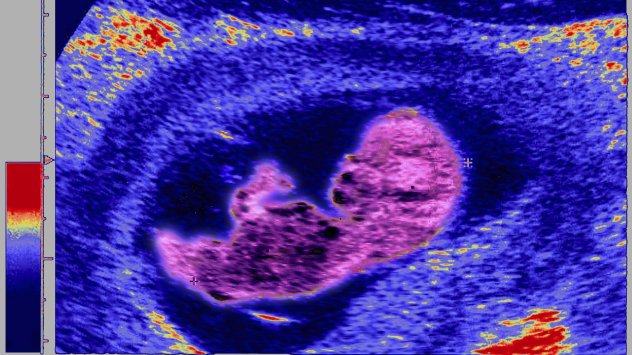

инвитро

Как нарастват запасите от яйцеклетки в Хонконг?